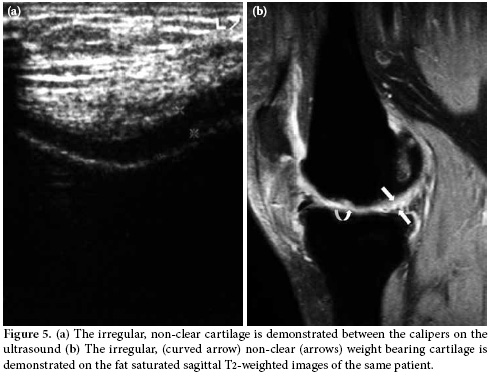

In the second position, the weight bearing medial and lateral femoral condylar cartilage thickness and clarity were evaluated with the knee in maximum flexion. The femoral condylar cartilage was measured on the weight-bearing area approximately 1.5 cm away from the intercondylar notch (Figure 3). The cartilage morphology was assessed using a scale: 1 for regular-clear (Figure 4a, b) and 0 for irregular, non-clear (Figure 5a, b). Finally, all the patients were evaluated for popliteal cysts with the knee extended in a prone position, and any presence of popliteal cysts was recorded.